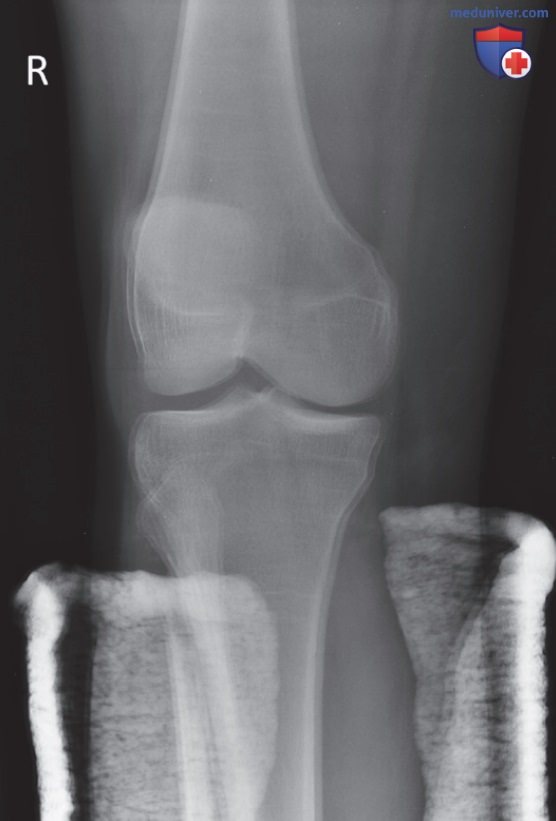

Пространственное разрешение рентгенограммы при оценке ее качества

Рисунок 7. Рентгенограмма правого коленного сустава в косой передне-задней проекции, демонстрирующая произвольное движение пациента.